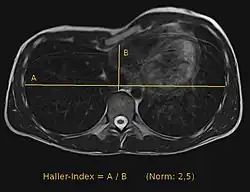

Anhand einer CT-Untersuchung oder einer Kernspintomografie lässt sich der Haller-Index ermitteln. Dieser Index wird weithin als Angabe für das Ausmaß der Trichterbrust verwendet. Er errechnet sich als der weiteste Abstand zwischen rechten und linken Rippen geteilt durch den kleinsten Abstand zwischen Brustbein und Wirbelsäule.[5] Ein anderes, mit einfacheren Mitteln zu bestimmendes Maß für die Tiefe der Trichterbrust ist der Abstand zwischen dem tiefsten Punkt der Trichterbrust und einem quer über die Brustwarzen gelegten Lineal.[6] Manchmal wird dieser Wert auch durch die Gesamttiefe des Brustkorbs dividiert.[7]